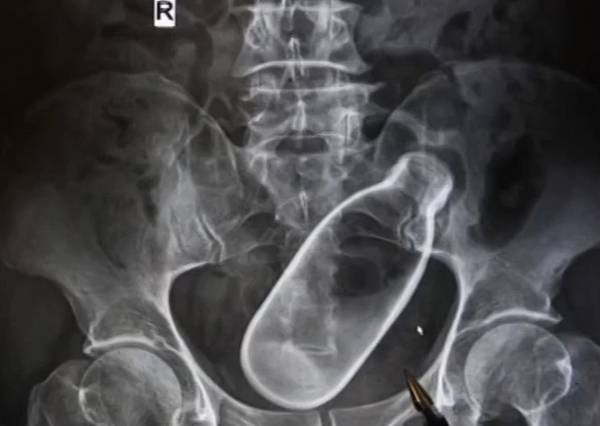

แกลเลอรีรูปภาพ พิเรนทร์!! หนุ่มใหญ่ยัดขวดเข้าทวารเอาไม่ออก